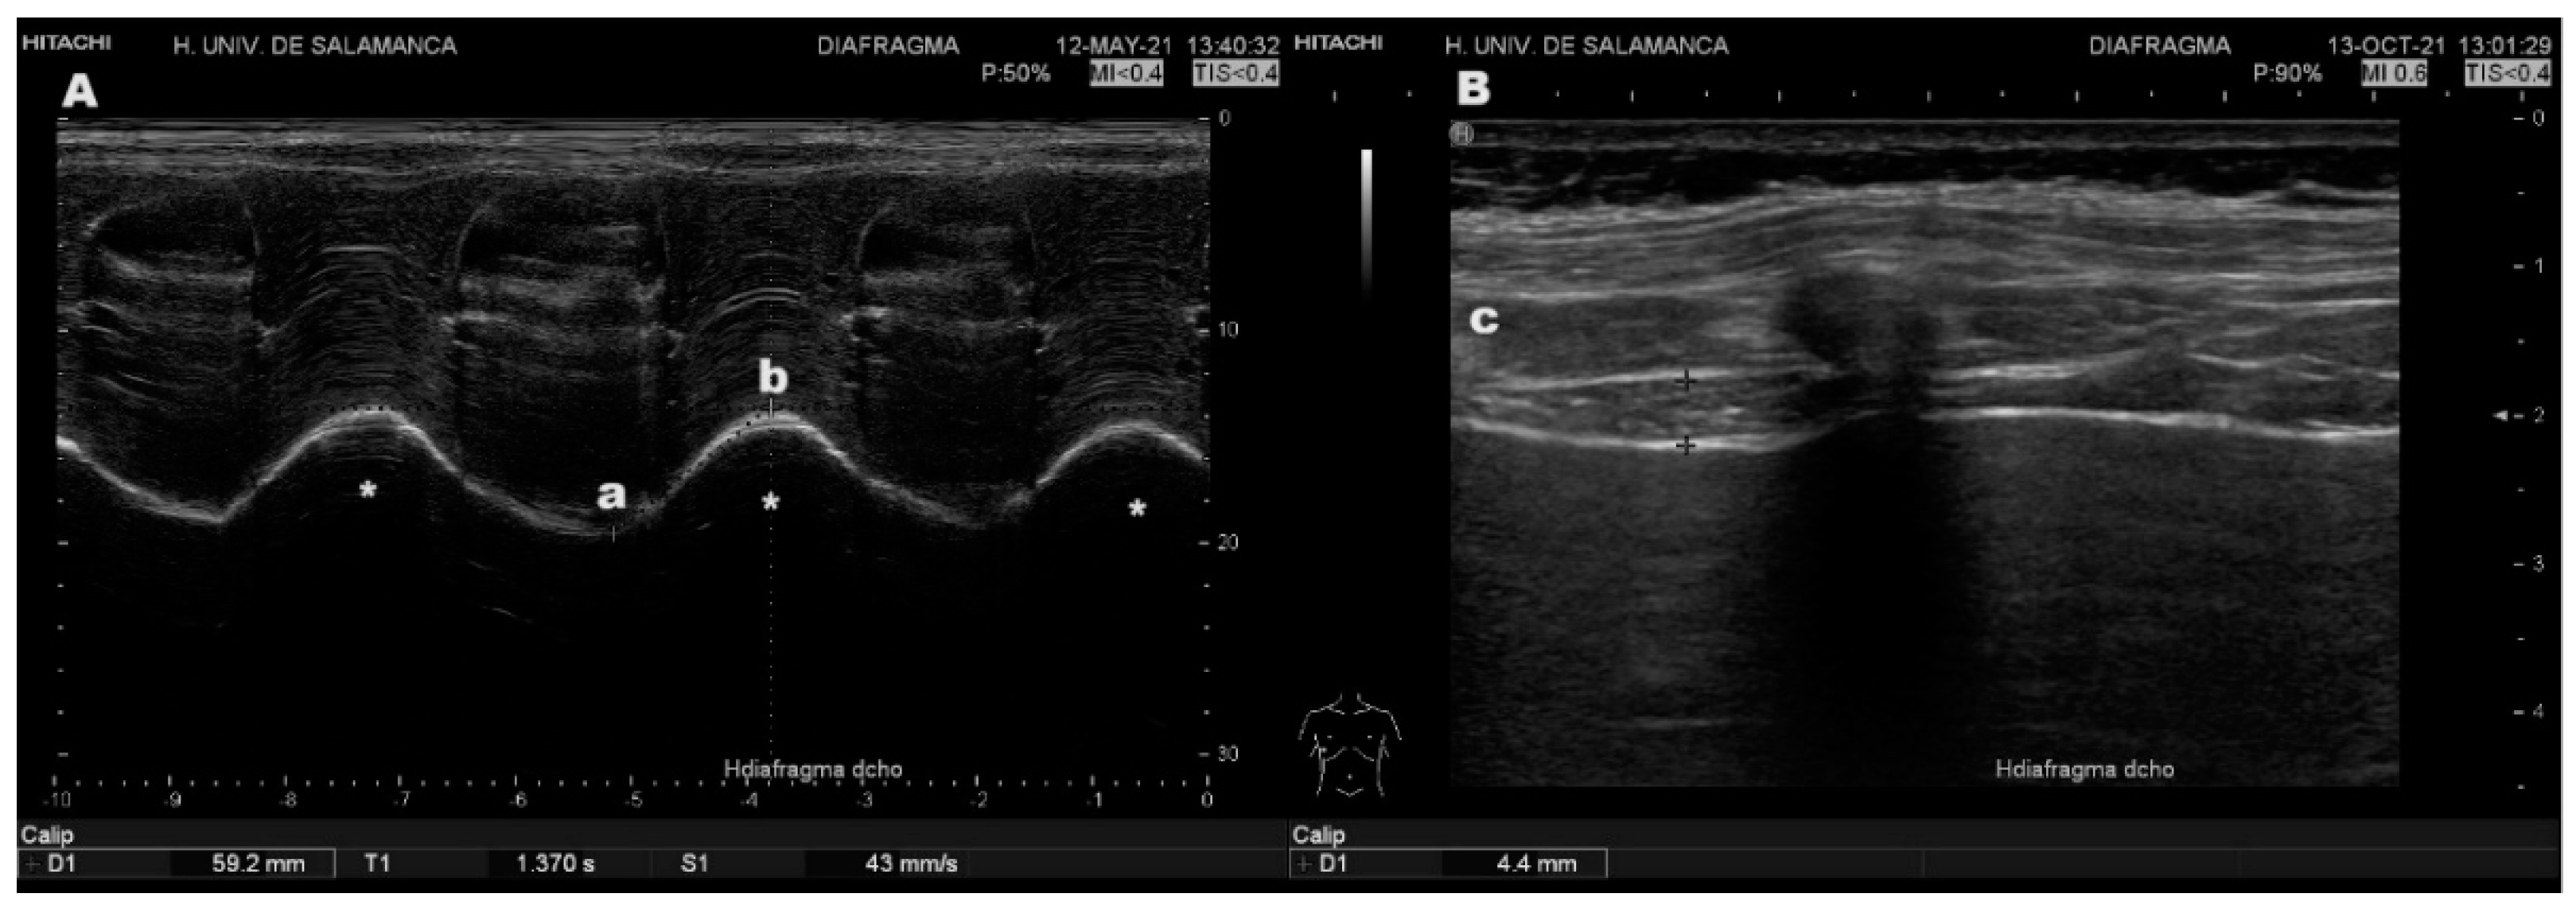

14K Yellow Gold 2mm Open Curb Link Chain 18 Inches| Sarraf.com, Evaluation of Diaphragmatic Ultrasound in Respiratory,